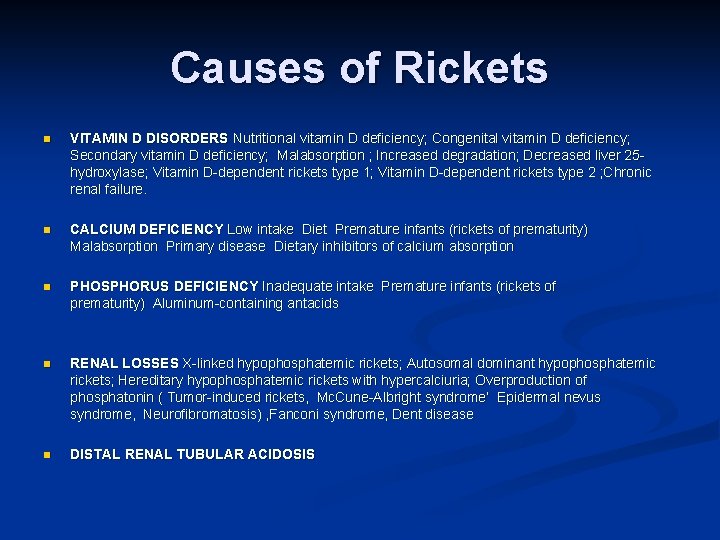

Causes of Rickets n VITAMIN D DISORDERS Nutritional vitamin D deficiency; Congenital vitamin D deficiency; Secondary vitamin D deficiency; Malabsorption ; Increased degradation; Decreased liver 25 hydroxylase; Vitamin D-dependent rickets type 1; Vitamin D-dependent rickets type 2 ; Chronic renal failure. n CALCIUM DEFICIENCY Low intake Diet Premature infants (rickets of prematurity) Malabsorption Primary disease Dietary inhibitors of calcium absorption n PHOSPHORUS DEFICIENCY Inadequate intake Premature infants (rickets of prematurity) Aluminum-containing antacids n RENAL LOSSES X-linked hypophosphatemic rickets; Autosomal dominant hypophosphatemic rickets; Hereditary hypophosphatemic rickets with hypercalciuria; Overproduction of phosphatonin ( Tumor-induced rickets, Mc. Cune-Albright syndrome’ Epidermal nevus syndrome, Neurofibromatosis) , Fanconi syndrome, Dent disease n DISTAL RENAL TUBULAR ACIDOSIS